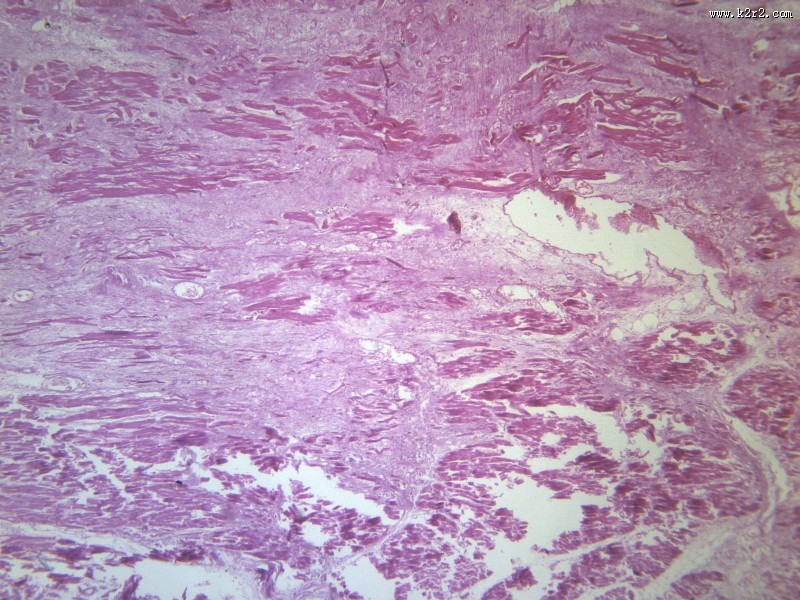

心肌梗死 - 第5张

第 5 / 12 张

图集中 / 共有 12 张图片

风湿性心肌炎

医学

显微切片

myocardial infarction

心肌梗死